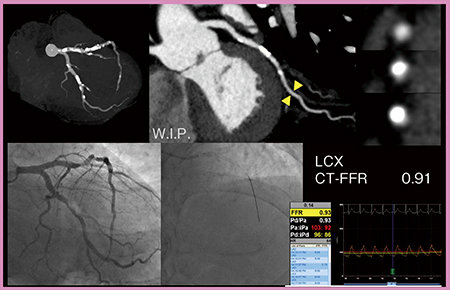

症例4は,労作時の息切れを主訴に狭心症(三枝病変疑い)精査目的で当院を受診した。カテーテルFFRにてLADとLCXを測定した結果,LADは0.73と低下しており,CT-FFRでも0.62と低下していた(図5)。LCXもCTAにて狭窄が疑われたが,カテーテルFFRは0.93,CT-FFRも0.91と正常であった(図6)。本症例は,CT-FFRの診断能でカテーテルFFRの省略が可能な症例と言える。

図6 症例4のLCXのカテーテルFFRとCT-FFR(W.I.P.)